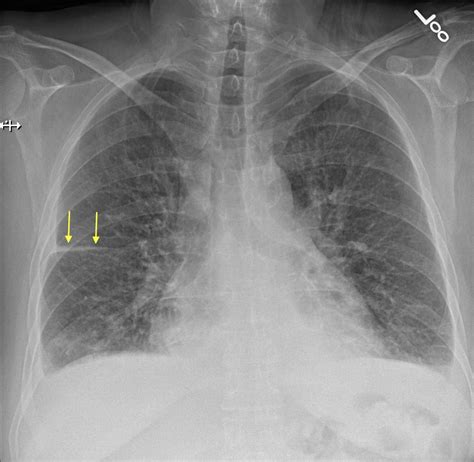

• Kerley B Lines: These are short, horizontal lines perpendicular to the pleural surface at the lung bases, representing thickened interlobular septa due to interstitial edema.

While the Pulmonary Edema Cxr is excellent at confirming the presence of fluid, determining the etiology is equally important. Cardiogenic pulmonary edema is typically associated with a widened cardiothoracic ratio (cardiomegaly) and vascular redistribution. In contrast, non-cardiogenic pulmonary edema, often seen in Acute Respiratory Distress Syndrome (ARDS), usually presents with a normal heart size, patchy or peripheral infiltrates, and an absence of pleural effusions.

Clinicians utilize the X-ray in conjunction with lab tests like Brain Natriuretic Peptide (BNP) to make a definitive diagnosis. If the heart shadow is enlarged, it strongly suggests a cardiac origin, whereas a normal-sized heart with widespread bilateral infiltrates warrants an investigation into sepsis, transfusion-related lung injury, or other non-cardiac triggers.

High-quality images allow for the visualization of delicate structures such as the fissures. Increased fluid in the interlobar fissures, known as a "fissural thickening," is another reliable indicator of interstitial pulmonary edema. Furthermore, the quality of inspiration affects the appearance of the lung fields; poor inspiration can create an artificial appearance of crowding of the bronchovascular markings, potentially mimicking mild congestion.